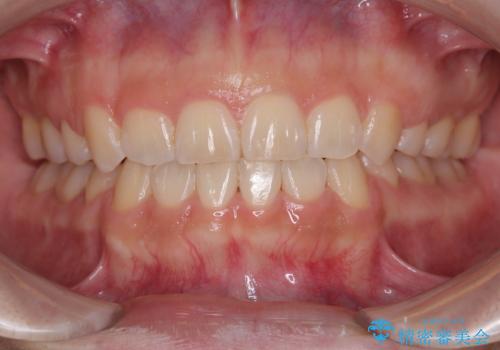

[ 矯正治療 ] 噛み合わせ前歯の見た目をきれいにしたい

![[ 矯正治療 ] 噛み合わせ前歯の見た目をきれいにしたいの症例 治療後](https://seimitsushinbi.jp/wp/wp-content/uploads/2025/08/IMG_3482-500x350.jpg?v=1754654765)